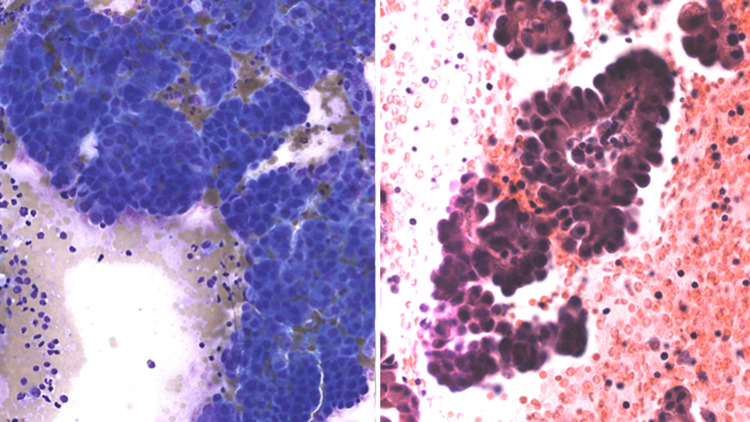

Fig. 5.

FNA of a cystadencarcinoma showing papillary features (left: Diff Quick stain, magnification × 10; right: H&E stain, magnification × 10)